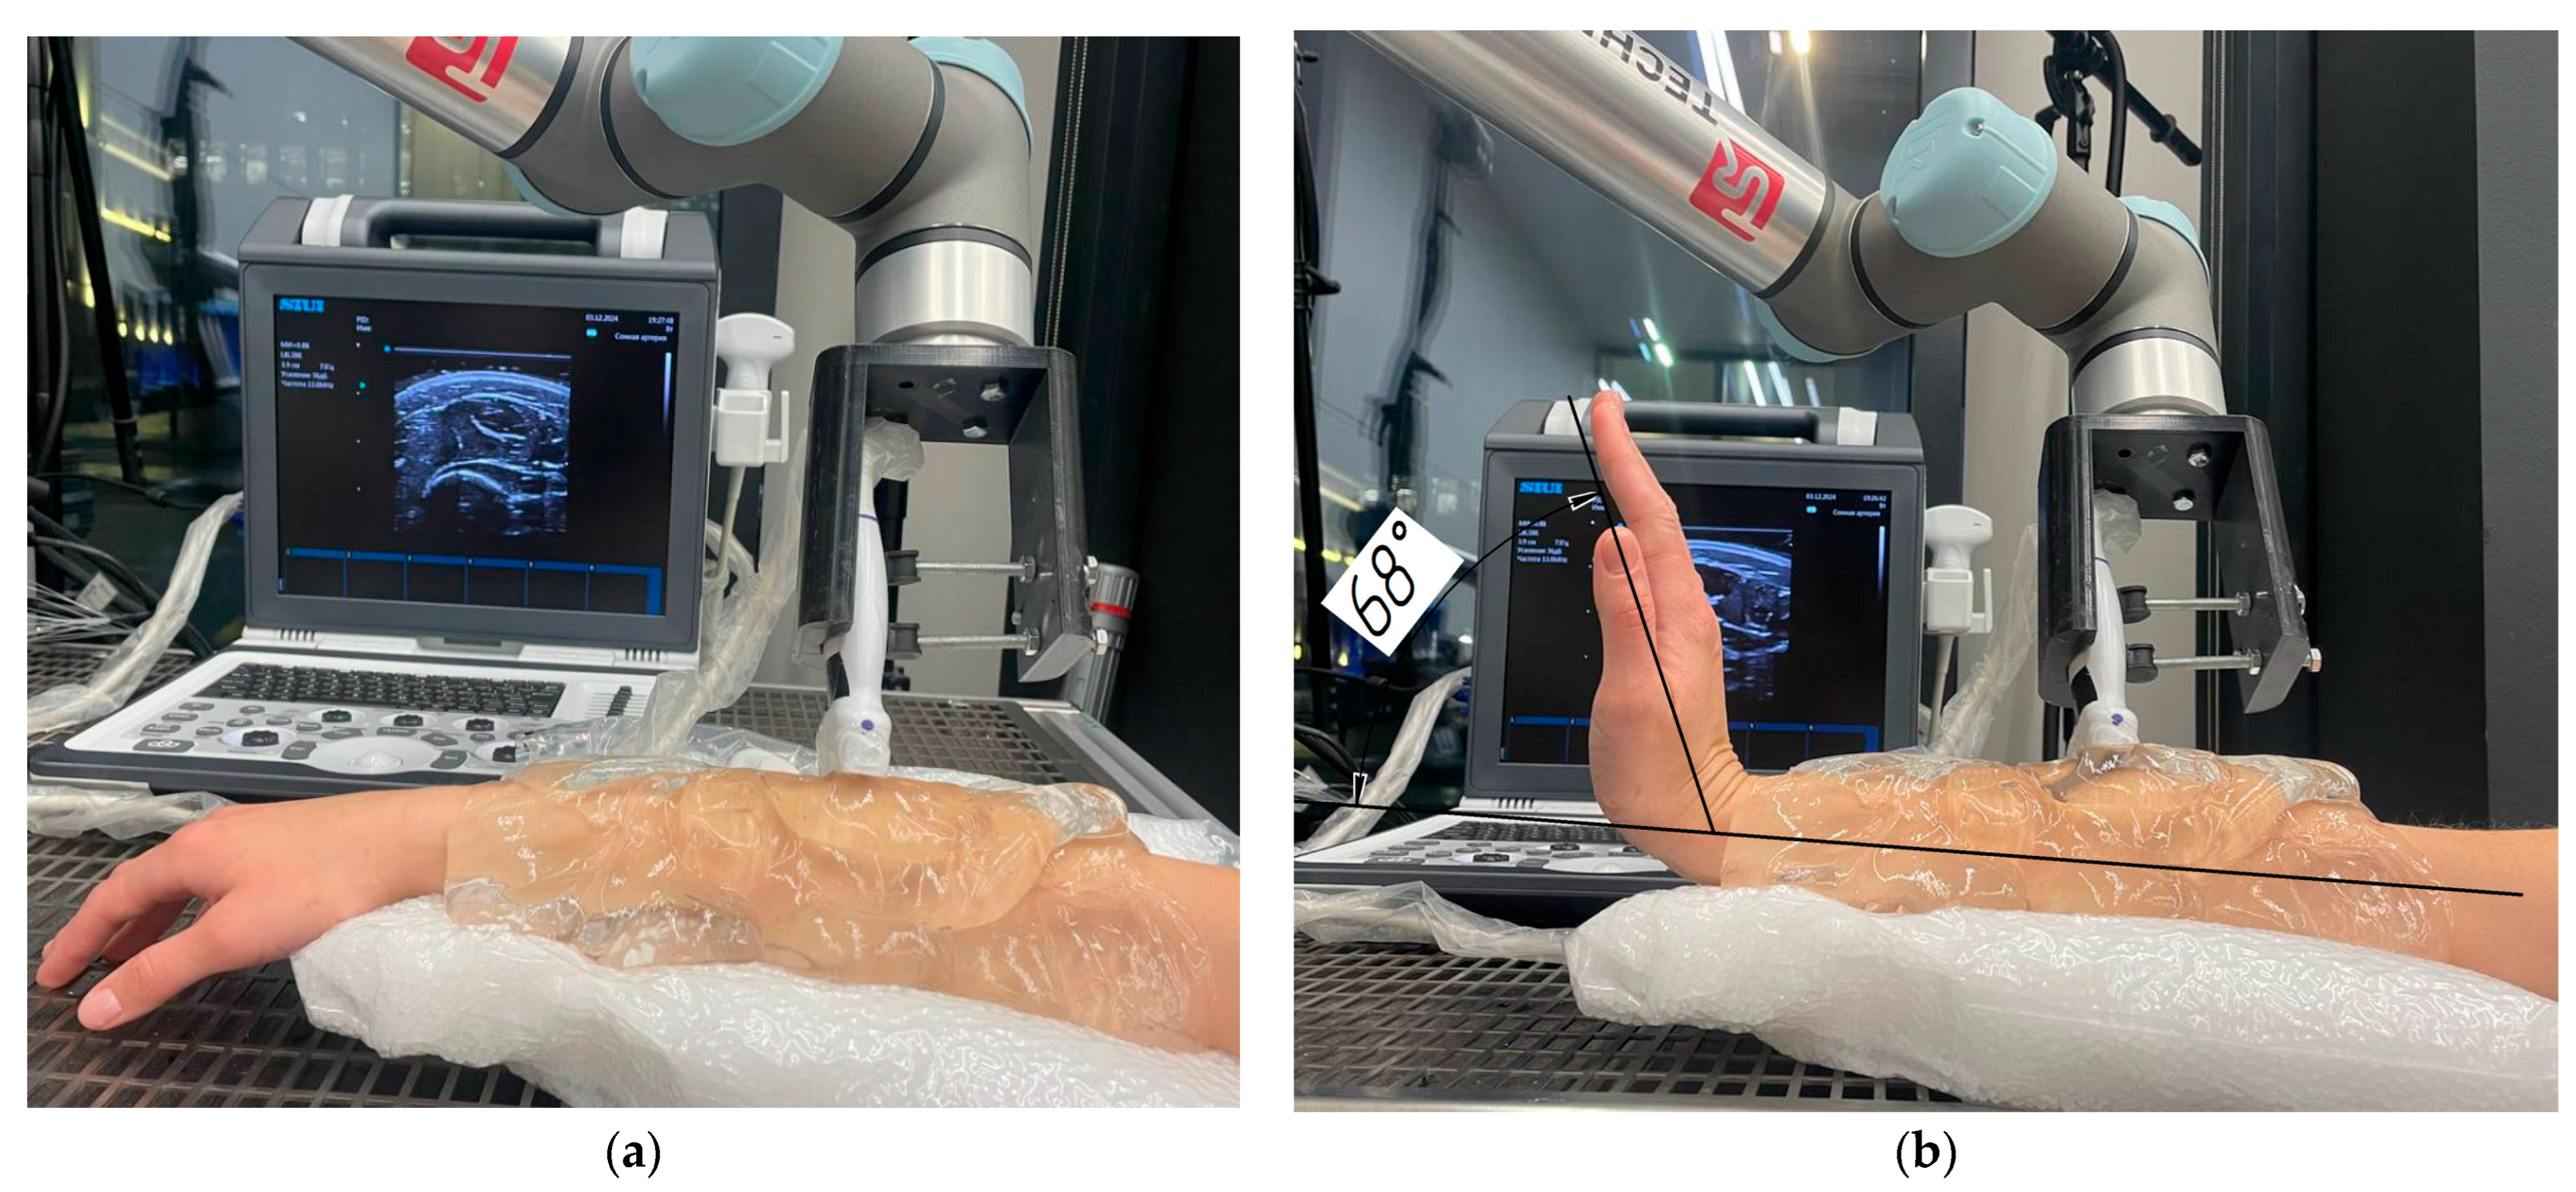

2.3. Robotic Scanning